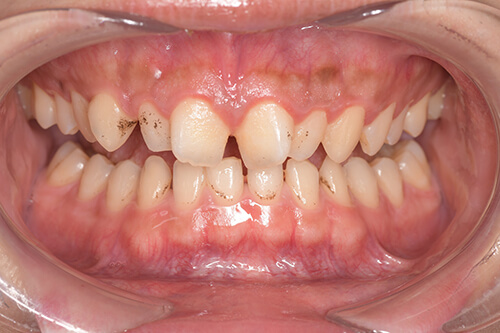

CASE 3

Before

After

基本情報

| 年齢・性別 | 30代・女性 |

| 主訴 | 定期検診 |

| 治療内容 | PMTC |

| 治療期間 | 60分 |

| 治療費 | 5,750円 |

| リスク・副作用 | しみる可能性があります。 |

| 治療方針 | PMTCでステインの除去。 |

| 担当者所見 | ステインが付きやすいため、3カ月毎の定期検診で除去する。 |